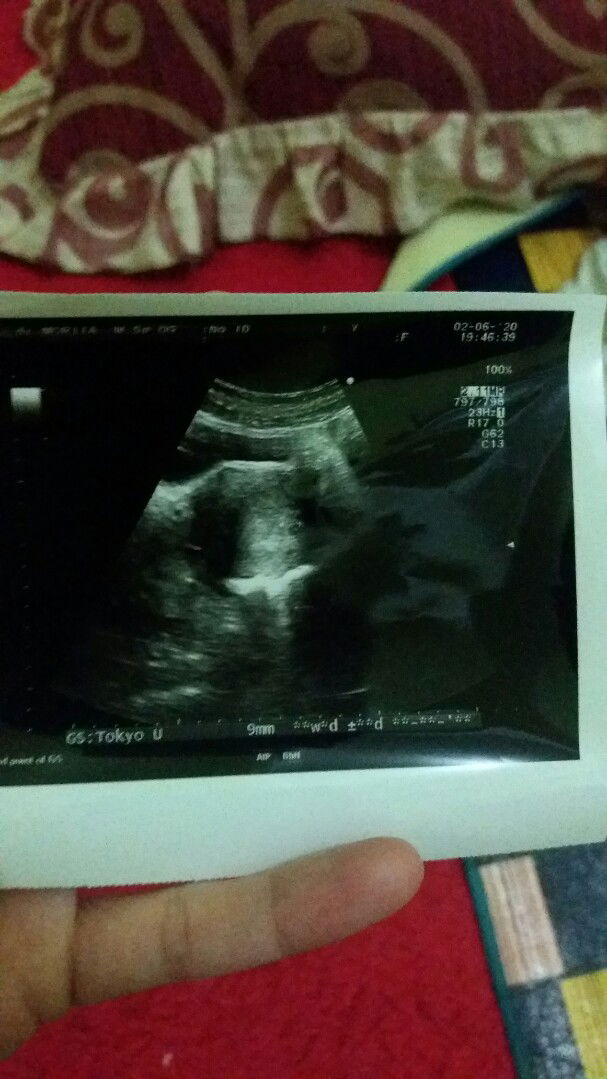

hasil USG

Bunda barusan saya abis dari dokter kehamilan saya 2 minggu .. saya awal haid 26 april sampe 3 mei. Adakah bunda2 disini mengerti hasil USG soalnya tadi lupa gak nanya ke dokternya

usg

Bunda bunda barusan saya abis dari dokter dan langsung USG perkiraan dokter usia kandungan baru 2 minggu.. saya haid pertama 26 april sampe 3 mei .. adakah yang tau maksud tulisan disebelah kanan itu apa? Soalnya tadi lupa gak nanyain.. makasih bunda